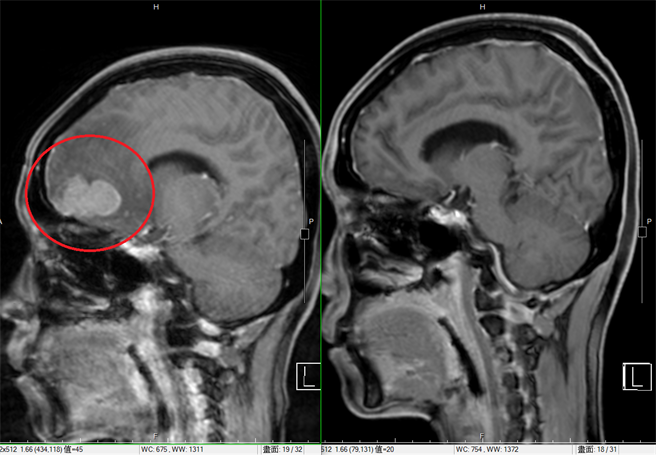

鍾道聲主任表示,以新一代影像導引弧形放射治療腦腫瘤,可降低海馬迴的放射劑量,減少對記憶及認知功能傷害。(圖左為術前,圖右為術後。圖/恩主公醫院提供)

鍾主任進一步說明,過去對於多顆腦腫瘤的處置,全腦放射治療是標準療程,但是對記憶力、語言等神經功能影響較大,特別是腦部海馬迴負責認知及執行能力的管控,稍一不慎就會傷及重要神經。不過隨著醫材科技進步,藉由新一代影像導引弧形放射治療,可降低對海馬迴的放射劑量,就能減少對記憶及認知功能傷害,讓癌細胞的腦轉移獲得控制,同時讓病人有較佳的預後生活品質。